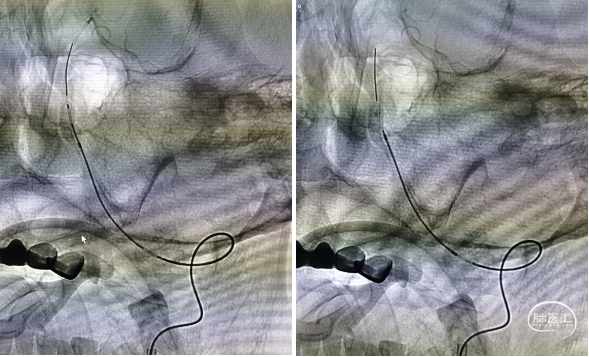

三型弓,最终采用泥鳅导丝、4F MPA1、6F Envoy同轴技术送入左侧椎动脉

造影提示右侧椎动脉闭塞,左侧椎动脉V4多发重度狭窄,并V4段夹层动脉瘤